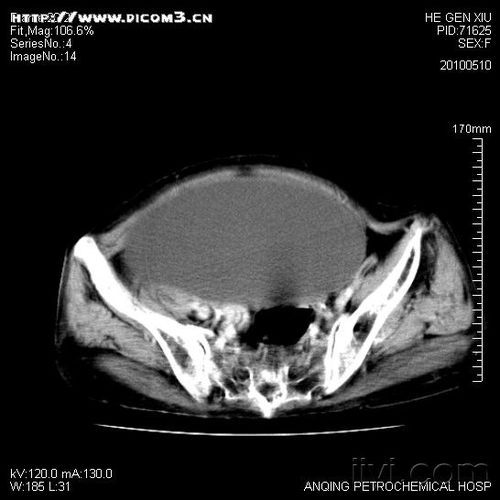

2. 肿瘤诊断

CT医学影像系统可以检测肿瘤的大小、形态、位置等信息,对于肿瘤的早期诊断和分期具有重要意义。